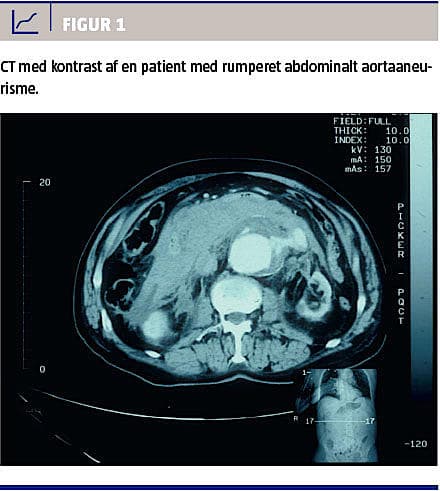

De fleste abdominale aortaaneurismer (AAA) er asymptomatiske; ruptur (RAAA) er oftest det første og eneste symptom og medfører en akut livstruende blødning (Figur 1). Akut intervention kan standse den retroperitoneale blødning og derved redde patientens liv. Indtil for nylig var åben operation den eneste akutte behandlingsform for RAAA i Danmark, men den er forbundet med en mortalitet på ca. 35%. Siden 1994 har man dog vidst, at endovaskulær behandling af AAA (EVAR) ved ruptur (REVAR) er mulig [1]. Man har sidenhen i flere studier fundet, at